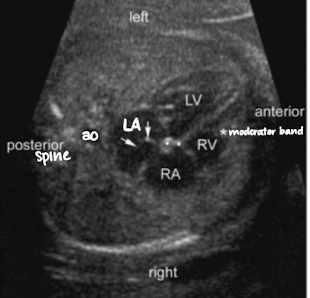

LA (left atrium)

receives blood from pulmonary veins (some) and foramen ovale (most)

sends oxygenated blood to LV via bicuspid/mitral valve (b/w LA and LV)

LV (left ventricle)

receives oxygenated blood from LA

sends oxygenated blood to the body via AO ← LVOT

T/F: LA is closest to the spine and AO

true

T/F: RV is most anterior to fetal body